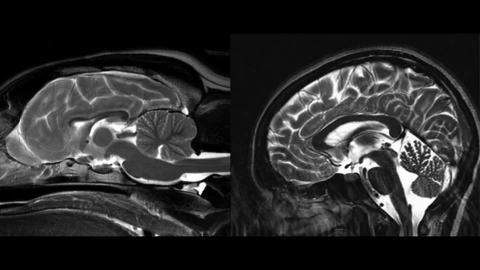

That’s where the MRI comes in. Although the machine can’t detect individual neurons, it can tell how they’re connected to each other. From there, scientists can deduce how the brain is functioning.

For this research, the scientists tried to identify parts of the dog brain that are analogous to the human brain. They ran similar types of experiments that they perform on humans in an MRI and tweaked them slightly for dogs.

The original experiments were centered on reward processing. They showed the dog an object and looked at the reward processing region of the brain for increased activity. “So, in some sense, we can understand what a dog is thinking and feeling,” said Gregory.

Since research began, the experiments have evolved from basic reward processing to complicated questions like how dogs see the world and process speech. They’ve even found evidence that dogs experience basic emotions.

In the experiment above, they’ve associated this giraffe object with a treat. Then, they show two- and three-dimensional versions of the same object. Human brains can differentiate between the two dimensions, and they’re seeing if a dog brain can do that as well.